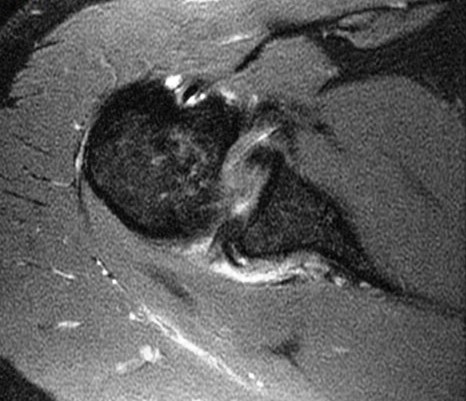

Discussion

Anterior humeral impaction fracture of the lesser tuberosity and posterior labrum tear. The periosteum of the scapula looks intact so maybe should be called a reverse Perthes lesion. Injury occurs when a posterior force occurs to the shoulder (front to back) when the shoulder is internally rotated and flexed. Classic examples are tonic clonic seizure with the patient falling with decorticate rigidity forward and hitting the ground. Also American football lineman in 3 point stance (internal rotation and some flexion) hit by another player moving towards him when the ball is hiked. Typically the other player is as large as a refrigerator.

Diagnosis

Reverse bankart and hill sachs lesions